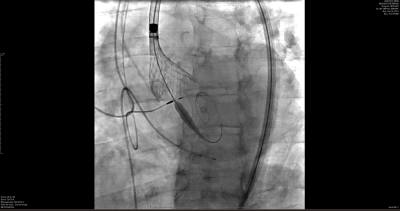

This minimally invasive procedure involves replacing a damaged aortic valve with a new one through a small incision in the groin, in most cases.

“When the aortic valve becomes very tight and doesn't open well, people experience being tired all the time, they have decreased energy, decreased exercise capacity, shortness of breath, chest pain, and then, more dangerously, may pass out,” Dr. Hyde said. “Most of the time, the diagnosis is suspected by symptoms and a loud murmur, but confirmation is made by an echocardiogram. The TAVR itself is where we go in the patient's groin, into the blood vessel and deploy a new valve inside their old valve that pushes the tight, stenotic valve out of the way, and then the new valve takes over.”